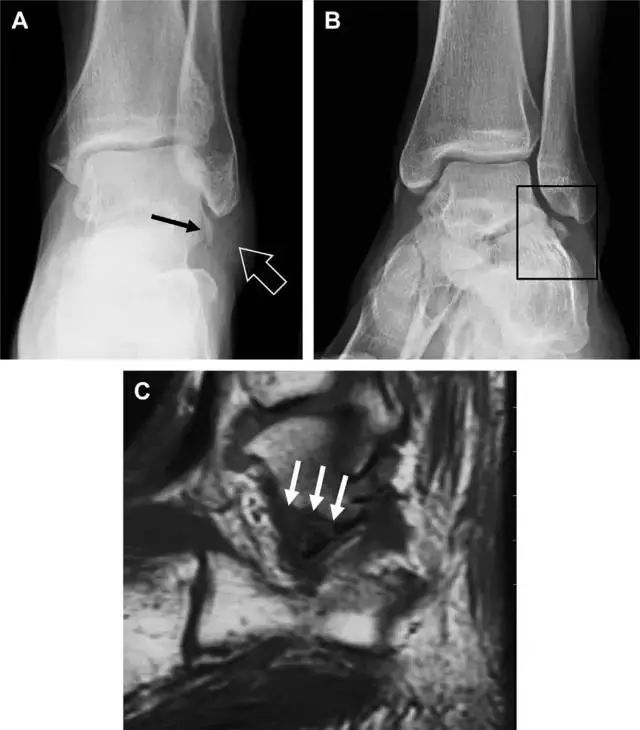

跟骨前突骨折

呈 Y 形的分歧韧带附着于跟骨前突上,是维持踝关节跖屈和背屈稳定性的重要结构。跟骨前突骨折常发生于足跖屈内旋、分歧韧带被牵拉时,或者足背屈外旋、骰骨和距骨挤压前突时。而这些骨折在初次 X 线检查时常常被漏诊掉。踝部侧位片诊断这些骨折最佳,准确诊断的关键点在于,必须仔细查看是否存在骨皮质中断(图 6)。如果侧位片可疑,建议加做斜位片协助诊断。

图 6 跟骨前突骨折。A 侧位片示跟骨前突骨折(箭头),与舟骨的重叠使骨折显示模糊;B 另一位患者的侧位片示内翻损伤所致的骨折(箭头),这种损伤机制引起小块的骨折。

趾短伸肌跟骨撕脱性骨折

另一种重要的跟骨撕脱性骨折,于足内翻时发生在趾短伸肌的起点处。观察来自跟骨背外侧的、不同大小的骨折块,前后位 X 片最适合不过了(图 7)。

图 7 溜冰受伤的患者,趾短伸肌跟骨撕脱性骨折。正位片示 2 个骨折块(箭头)来源于跟骨前外侧、趾短伸肌的起点处。踝关节外侧远端是否存在软组织水肿是一个重点观察点。